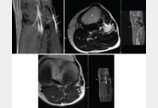

“말초신경 마비” 희귀질환 ‘신경내 결절종’…원인 찾았다가톨릭대학교 서울성모병원은 손병철 신경외과 교수가 최근 미국 메이요 클리닉(Mayo Clinic) 신경외과 로버트 스피너(Robert J. Spinner) 교수팀과의 공동 연구를 통해 말초신경 마비를 유발하는 신경내 결절종(intraneural ganglion cyst)의 복잡한 발생…2026-01-13 10:29:19